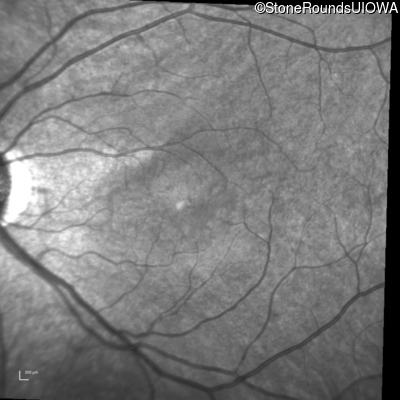

Infrared Fundus Photograph - Right - 20/40 +1

Exemplar

Infrared Fundus Photograph - Left - 20/50